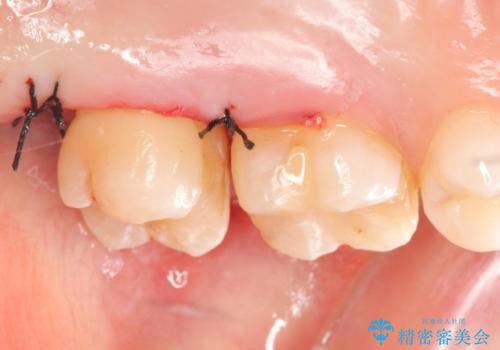

左上7近心の虫歯は歯茎より深く、歯茎を下げるため歯周外科を行いました。

術後歯肉の回復を待ち、左下6、7ともにセラミックインレーによる修復を行いました。

そのため当院では歯周外科手術(歯茎を下げる手術)や歯の挺出による、虫歯が歯茎より深いという問題の解決を推奨しております。